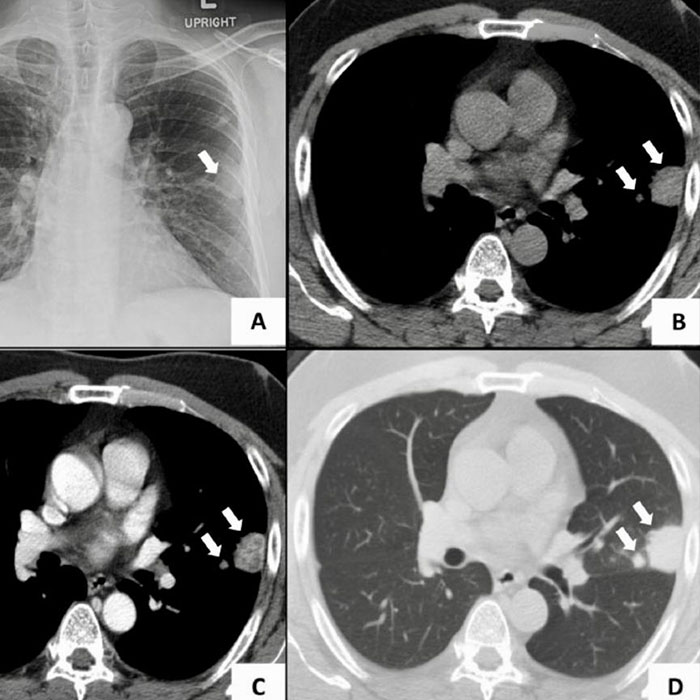

• Akciğer grafisi

• Bilgisayarlı tomografi

Görüldüğü üzere farklı şekillerde yapılabilecek görüntüleme işlemlerinde seçenekler oldukça fazladır. Hastalar için en uygun olan yönteminin belirlenmesi de böylece kolaylaşmaktadır. En yaygın kullanılan radyolojik tetkik olarak dikkat çeken akciğer grafisi ile birlikte akciğer ve kalp gibi hayati öneme sahip organların kontrol edilmesi ve kemik yapılarının incelenmesi sağlanmaktadır.